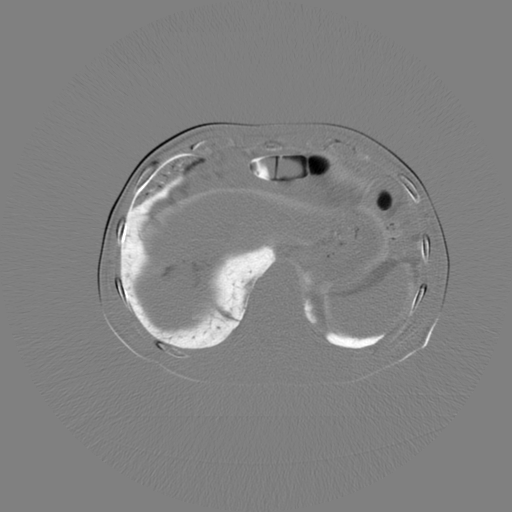

5.4 Real Knee Data with Metal Implants

Refer to caption

Figure 13: Three examples of synthetic perspective projection images for training, intensity window: [0, 4]. The appearance (e.g., image contrast and metal image resolution) of such DRR training images is different from that of real projection images in Fig. 14.

The complementary view setting for learning perspective deformation is also evaluated on real CBCT projection data. In this evaluation, real CBCT projection data from a dataset of knees with metal implants is used for testing, while DRRs created from volumetric CT datasets with inserted metals is used for training. Three exemplary DRR perspective projection images for training are displayed in Fig. 13, in which synthetic metal implants are inserted [34]. The appearance, e.g., image contrast and metal image resolution, of such DRR training images is different from that of real projection images in Fig. 14. In Fig. 14, the results for three knees, with and without metal implants, are displayed. The first and second rows are the 0superscript00^{\circ} and 180superscript180180^{\circ} perspective projections, respectively, rebinned to the virtual detector with geometric calibration based on their respective principal points and projections of the world origin. The third row displays their difference images, where the magnitude of deviation increases from the center towards the outside like it does in DRRs with an ideal scan trajectory (e.g., Fig. 6(e)), although real projection data suffer from various physical effects like beam hardening and Poisson noise. The fourth row displays the RGB stacks of 0superscript00^{\circ} and 180superscript180180^{\circ} perspective projection images. The magenta and green regions indicate structures with considerable perspective deformation, for example, the knee patella in Fig. 5.4, the top parts of the two metals in Fig. 5.4, and the bottom two screws in Fig. 5.4. The fifth row displays reference images, which are orthogonal projections of iterative reconstruction volumes from measured CBCT projection data. In the reference images, a total of five landmarks are selected, with the positions being marked by the green dots: In Fig. 5.4, two positions at the edges of the knee patella are marked; In Fig. 14(e) and Fig. 14(f), one position at the left edge of the fibula is marked for each image. In addition, a rectangular frame for the two metals is marked by the green dashed lines, while its width and height are indicated by the green solid lines, which are 29.71 mm and 111.99 mm, respectively. In Fig. 14(f), the centerlines of the bottom two screws are sketched by the green lines, which have the lengths of 17.14 mm (middle screw) and 19.38 mm (bottom screw). The corresponding rectangular frame for the two metals and the screw centerlines in the perspective projection images are marked as well, but in red color. In Fig. 14(a), the width and height of the metals are 32.56 mm and 109.85 mm, which have deviations of 2.84 mm and -1.95 mm to the reference ones, respectively. In Fig. 14(b), the centerline lengths are 18.91 mm and 19.54 mm, which have deviations of 1.77 mm and 0.16 mm, respectively. Although the bottom screw has little length deviation to the reference, the orientations of both screws are obviously deviated. The sixth row shows the results of Pix2pixGAN using 0superscript00^{\circ} and 180superscript180180^{\circ} polar inputs. For all of the landmarks, the green reference dots are all located accurately in the Pix2pixGAN images. The rectangular reference frame also accurately covers the metals in Fig. 14(g). In Fig. 14(h), although the two red centerlines do not exactly overlap with the green one, they are very close in lengths and orientations. Please zoom in for better visualization.